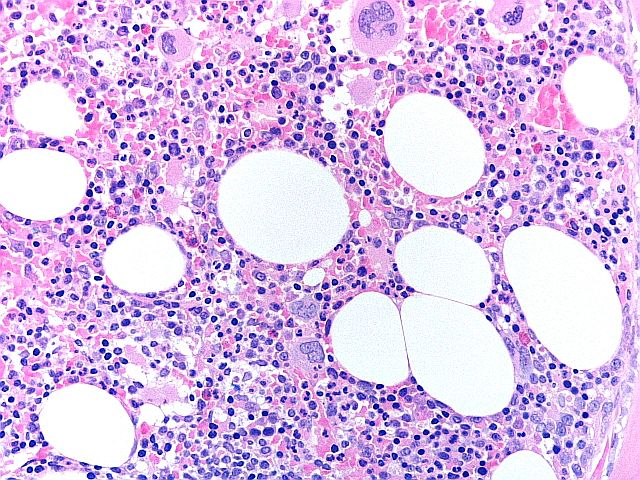

Esquema H&E - BMT

Esta es una excelente preparación de una biopsia de médula ósea, con tinción equilibrada de hematoxilina y eosina, buen detalle de la cromatina y tinción selectiva de los tipos celulares del tejido de la médula ósea. Esta preparación obtuvo una puntuación de 9/10 en la evaluación.